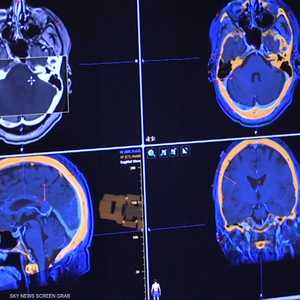

وقد راجع الباحثون النقاط الخاصة بمؤشر كتلة الجسم لدى الأطفال واستخدموا صور الرنين المغناطيسي للدماغ، لتحديد التغييرات الحاصلة في أدمغتهم، وخلصوا إلى أن زيادة الوزن في مرحلة الطفولة مرتبطة بتراجع صحة الدماغ، وضعف الأداء الإدراكي لا سيما في مجال الدراسة أو الوظائف الموكلة للطفل.